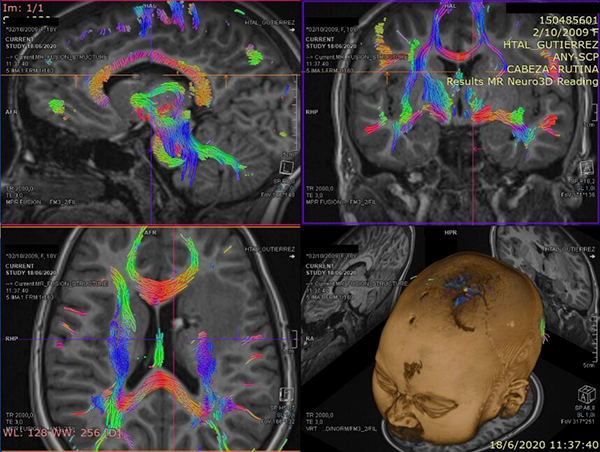

La paciente de 12 años presentó cefaleas, hemiparesia y pérdida de conciencia aguda que requirió soporte de Asistencia Respiratoria Mecánica durante tres días, dos meses previos a la cirugía. Debido al volcado ventricular se colocó un Drenaje Ventricular al exterior. Luego del episodio agudo la paciente se recuperó sin déficit motor. Mediante Resonancia Magnética por Imágenes (RMI) se diagnosticó un Cavernoma adyacente a la CI y sobre el Núcleo Caudado (NC) (Figura 1 A, B y C). El estudio de la RMI por Tensor de Difusión (Tractografía) expuso que la vía motora izquierda no estaba interrumpida completamente, quizá desplazada hacia lateral respecto de la rodilla de la CI (Figura 2).

Figura 2: Estudio de Tensor de difusión. Nótese la atenuación de la señal del haz motor en el hemisferio izquierdo.